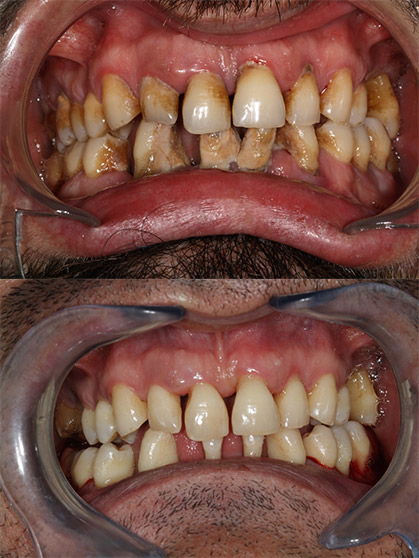

soins pratiqués

Parodontologie

Vos dents se déchaussent ? Vos dents bougent ? Vos gencives saignent ?

Il y a des solutions à la parodontie et des soins possibles après un bilan complet de votre potentielle parodontite au sein de notre cabinet : nettoyage des gencives en profondeur – surfaçage – élimination du tartre, greffe de gencive, greffe osseuse, freinectomie bébé – nourrisson – adolescent – adulte, dégagement de dents incluses

Les MALADIES PARODONTALES sont des infections chroniques des tissus de soutien des dents (os, gencive) dues à une accumulation de « bactéries » contenues dans la plaque dentaire. Cela aura un impact sur l’os qui entoure la racine des dents qui va se résorber créant des rétractions de gencive et des mobilités dentaires.

SAIGNEMENT . MOBILITÉ . PERTE DENTAIRE . BOURRAGE ALIMENTAIRE . SENSIBILITÉ . RETRACTION GENCIVE . MAUVAISE HALEINE . ABCÈS .

Chirurgie parodontale

Si le traitement de surfaçage n’a pas été suffisant, une étape parfois chirurgicale sera nécessaire sur certaines dents pour éliminer les tissus infectées sous la gencive en soulevant chirurgicalement la gencive.

Parfois, même si la maladie parodontale est stabilisée, certains sites autour des dents peuvent bénéficier d’une régénération osseuse par la mise en place de biomatériaux dans le défaut ce qui permet de renforcer la dent et revenir à une situation presque normale.